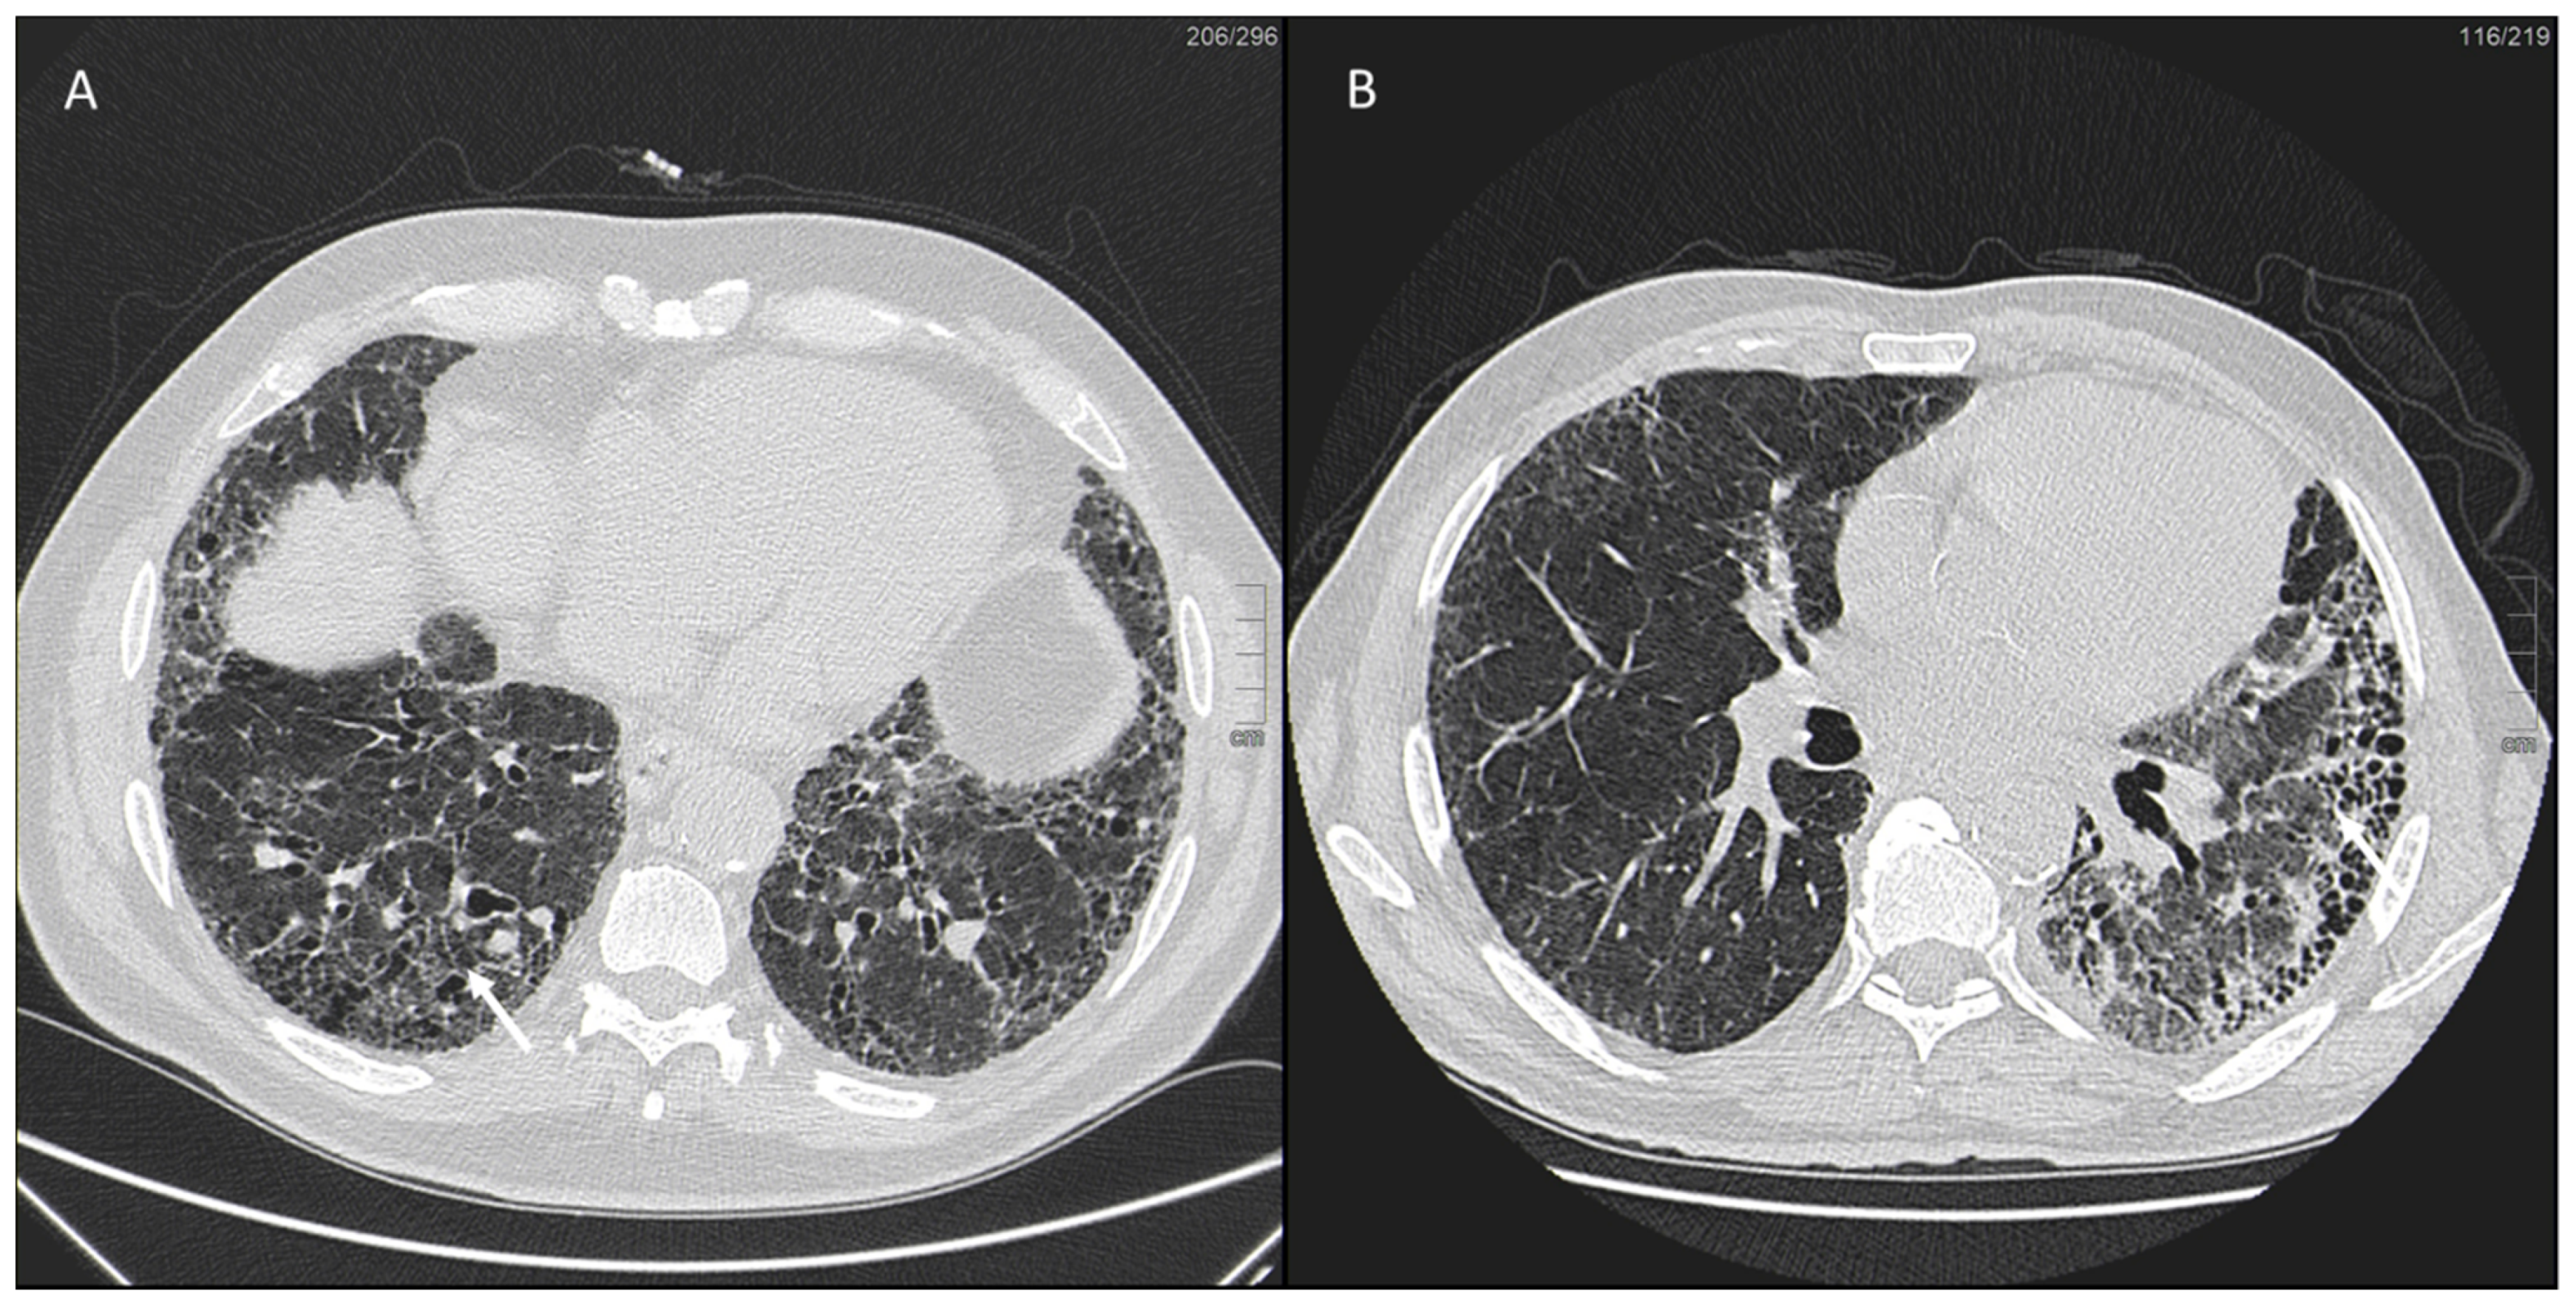

IPF is a chronic, irreversible, disabling disease with a fatal outcome characterized by a progressive decline in lung function. It is associated with a radiological pattern of usual interstitial pneumonia (UIP). In the literature, women have shown less fibrotic alterations than their male counterparts at HRTC (Figure 4).

Figure 4.

(A) Diffuse ground glass opacities with reticular thickening of the subpleural interstitium (white arrow), together with traction bronchiectasis in a case of pulmonary fibrosis with UIP pattern and smoking-related interstitial lung disease (ILD) in a female smoker. (B) A typical UIP pattern in a male smoker with idiopathic pulmonary fibrosis, together with diffuse ground glass opacities (white arrow) during an acute exacerbation.

A French multicenter prospective study [104] explored gender differences in an IPF cohort over a 5-year follow-up period. The cohort included 51 (22%) females and 185 (78%) males with a mean age at diagnosis of 70.1 ± 9.20 and 67.4 ± 10.9 years, respectively. At presentation, honeycombing and emphysema at HRCT were less common in females: (n = 40 (78.4%) vs. n = 167 (90.3%), p = 0.041) and (n = 6 (11.8%) vs. n = 48 (25.9%), p = 0.029), respectively. Fewer women than men also underwent transplantation during follow-up (n = 1 (1.96%) vs. n = 20 (10.8%), p = 0.039).